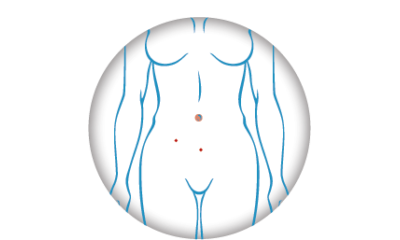

Chirurgie effectuée sous basse pression combinée à la micro coelioscopie (incisions 4X plus petites que les incisions en coelioscopie conventionnelle) pour réduire la douleur post-opératoire, réduire l’impact de la chirurgie sur le corps du patient. Pour une meilleure prise en charge ambulatoire.

Chirurgie générales et gynécologique

Découvrez les avantages de la chirurgie générale et gynécologique avec la Low Impact Laparoscopie.